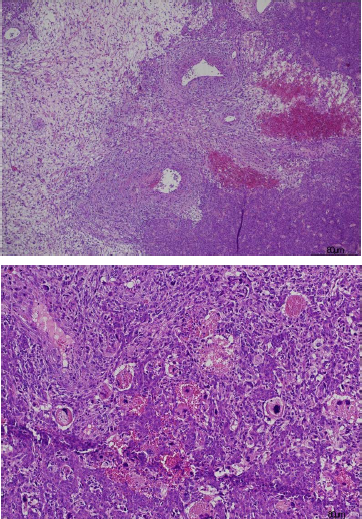

A 47-year-old woman was referred to our hospital for abdominal pain and moderate ascites. Tumor markers, including CA125 and alpha-fetoprotein, were normal. CT imaging revealed a large, heterogeneously enhanced pelvic mass (9 x 5 cm) adherent to the bowel, omentum, and left ovary. Surgical intervention included radical hysterectomy, bilateral oophorectomy, partial bowel and omental resection, and peritoneal biopsies. The tumor appeared to originate from the left ovary, with omental and bowel involvement. Macroscopically the main pelvic mass of 9 cm appeared to arise from the left ovary and omental involvement in the form of multiple nodules ranging in size from 0.6 to 3 cm, and bowel involvement showing retracted serosa were detected. The cut surface of the tumor revealed a tan-white lesion with extensive necrosis and hemorrhage. Microscopically areas of the tumor show features of conventional SFT with a patternless architecture and uniform fibroblastic morphology, along with prominent branching vessels (Fig. 1A). However, even within this component, there was transition to an area of tumor which was much more pleomorphic and showed a high mitotic rate (Fig. 1B). There is a very abrupt transition to a morphologically distinct component characterized by a fascicular spindle cell morphology, almost resembling a smooth muscle neoplasm, again with a high mitotic rate and, present within this fascicular component, there are small areas of ossification. In the SFT-like component, there was diffuse positivity for CD34 in the conventional areas, which decreases in the less differentiated areas and with greater pleomorphism. (Fig. 1C). Positivity for STAT6 is instead intense and diffuse in all components of the neoplasia. (Fig. 1D). The fascicular spindle cell area also shows focal positivity for SMA and desmin. Stains for MDM2, CDK4 and caldesmon are negative. The diagnosis was malignant SFT with dedifferentiation and focal osteoid deposition. This case is highly unusual due to its rare ovarian presentation and the abrupt transition from conventional SFT to a high-grade dedifferentiated component. The patient developed additional metastatic lesions one month after the diagnosis localized in peritoneum and liver. She chose to not undergo any treatment and passed away three months after the diagnosis.

Figure 1. (A) The neoplasia show areas with variable ovoid and spindle uniform cellularity in a patternless architecture. Prominent branching vessels are also present. (B) Dedifferentiated areas with greater pleomorphism and high mitotic activity.

Figure 1. (C) Diffuse positivity for CD34 in the conventional areas, which de-creases in the less differentiated component. A small area of ossification in also present in the image. (D)Intense and diffuse positivity of STAT6 in all the components of the neoplasia.